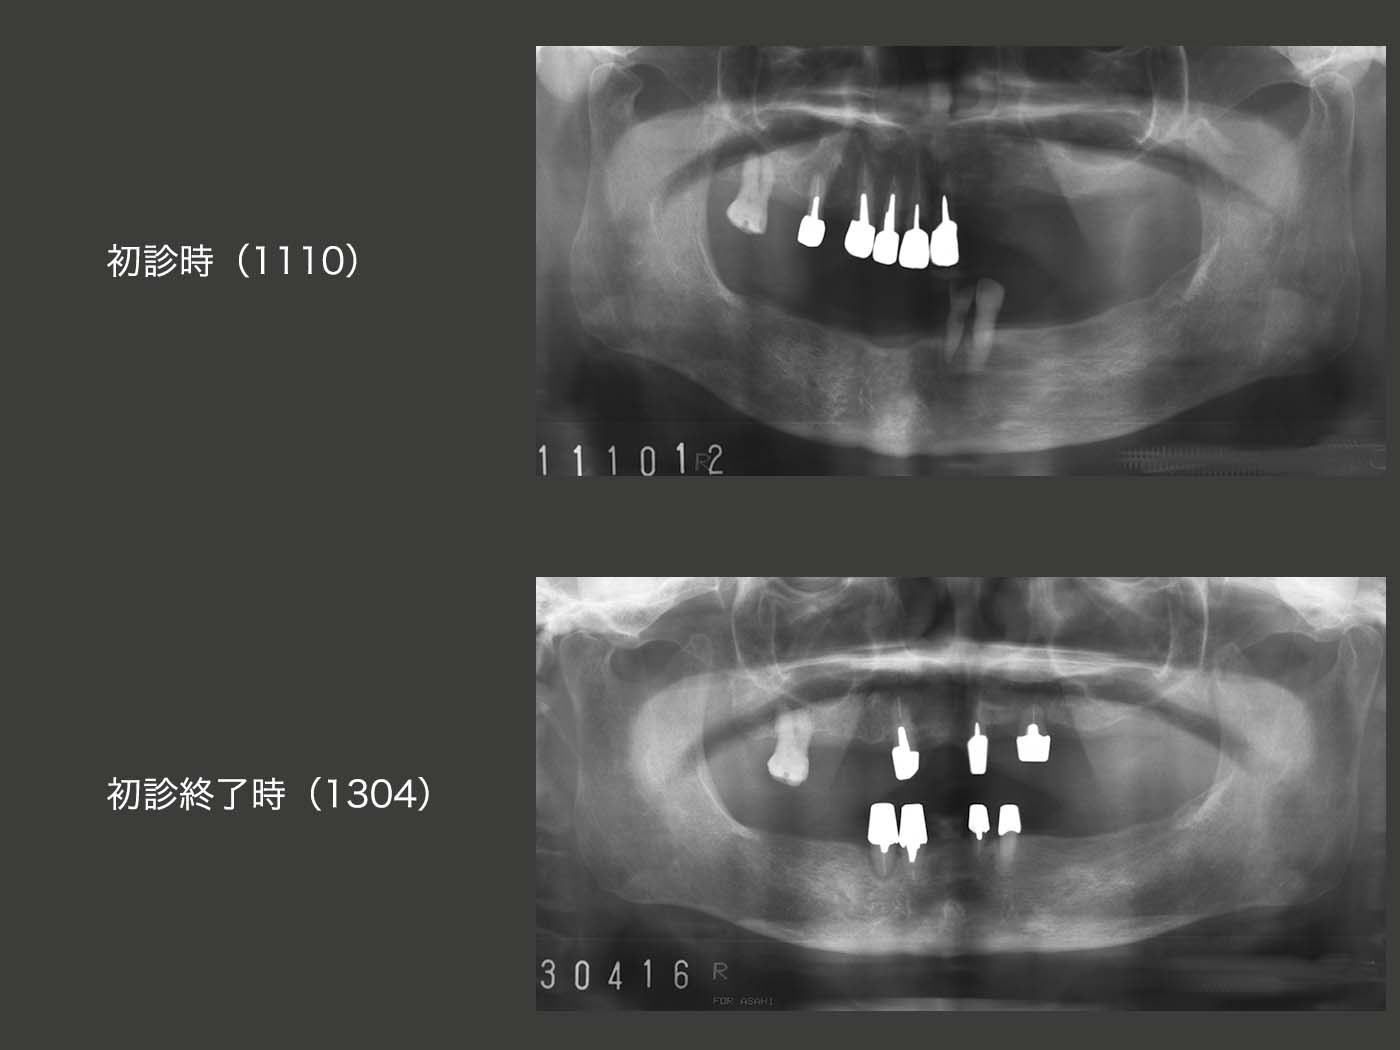

8.移植を3本行い、支台歯の配置を改善

2011年10月初診,76歳女性.10年位前から義歯を使用しておらず,唯一上下咬合している前歯で細々と食事していたが,痛みが生じ,限界に達したため来院.まず,義歯に対する反応をみるために,11月に暫間義歯を装着した.義歯を装着して食事は何とかとれるようになったが,義歯の大きさによる異物感,発音障害等が気になるとのこと.通常,片顎の四隅に歯があれば,義歯を安定させることができる.一歩譲って左右側に歯があれば,何とか義歯を安定させることができる.しかし片側だけでは,いくら歯の数が多くても,反対側の義歯の安定を得ることは難しい.

そこでまず,対合歯のない右上1,2に矯正的挺出力を加え,抜歯しやすいように細工したのちに,2012年2月に右下の顎堤に移植した.なお,矯正用のミニインプラントを植立し,移植歯の暫間固定を図った.

12年3月,今度は右上5に矯正的挺出力を加えたのち,4月に左上の顎堤に移植した.なお,受容側である左上の顎堤が狭かったので,顎堤を少し拡大した.さらに,移植歯と左上1とを暫間固定した.

初診時および初診終了時のパノラマX線写真の比較.歯の垂直・水平的配置は,初診終了後のほうが遥かに良い.ここで,インプラントを用いるほうがよいという意見もあると思う.それも一理であるし,否定もしない.しかし,移植でも対応可能であれば,移植の方が好ましいと考えている.

初診終了後の経過を示す.まず,2015年12月,右下4の移植歯が自然脱落してしまった.この歯は,初診終了時から歯の動揺がみられた.移植の手技が稚拙であったと言わざるを得ない.

つぎに,17年10月,左上1の内冠が歯冠破折し,コアごと脱離した.歯肉縁上歯質がないため,軸面のある内冠を再製作するのは難しい.そこで,支台歯に加わる側方力を少しでも少なくするために,根面アタッチメント(OPA)を装着した.なお,外冠をこのまま再利用できるというのも大きな利点であると同時に,根面アタッチメント周囲を開放できるのも大変好ましい.

18年12月,今度は左上3(移植歯)の動揺が著しくなり,抜歯となってしまった.左上3の歯周ポケットは,移植後は3mm以下で,この状態が12年から15年まで続いた.15年7月に最大5mmになり,18年12月に最大7mmに達した.支台歯の清掃は十分に行われていることから,抜歯の原因は,咬合力に耐えられなかったからと推測される.

20年7月現在,口腔内はとりあえず安定している.それにしても,移植した3本中,2本が抜歯となってしまったことについては,力に負けてしまったことが一番の要因と思われる.また,如何せん移植歯の歯根が短いことも影響しているように思われる.もっと歯根を深く埋入させるべきであったと反省する次第である.